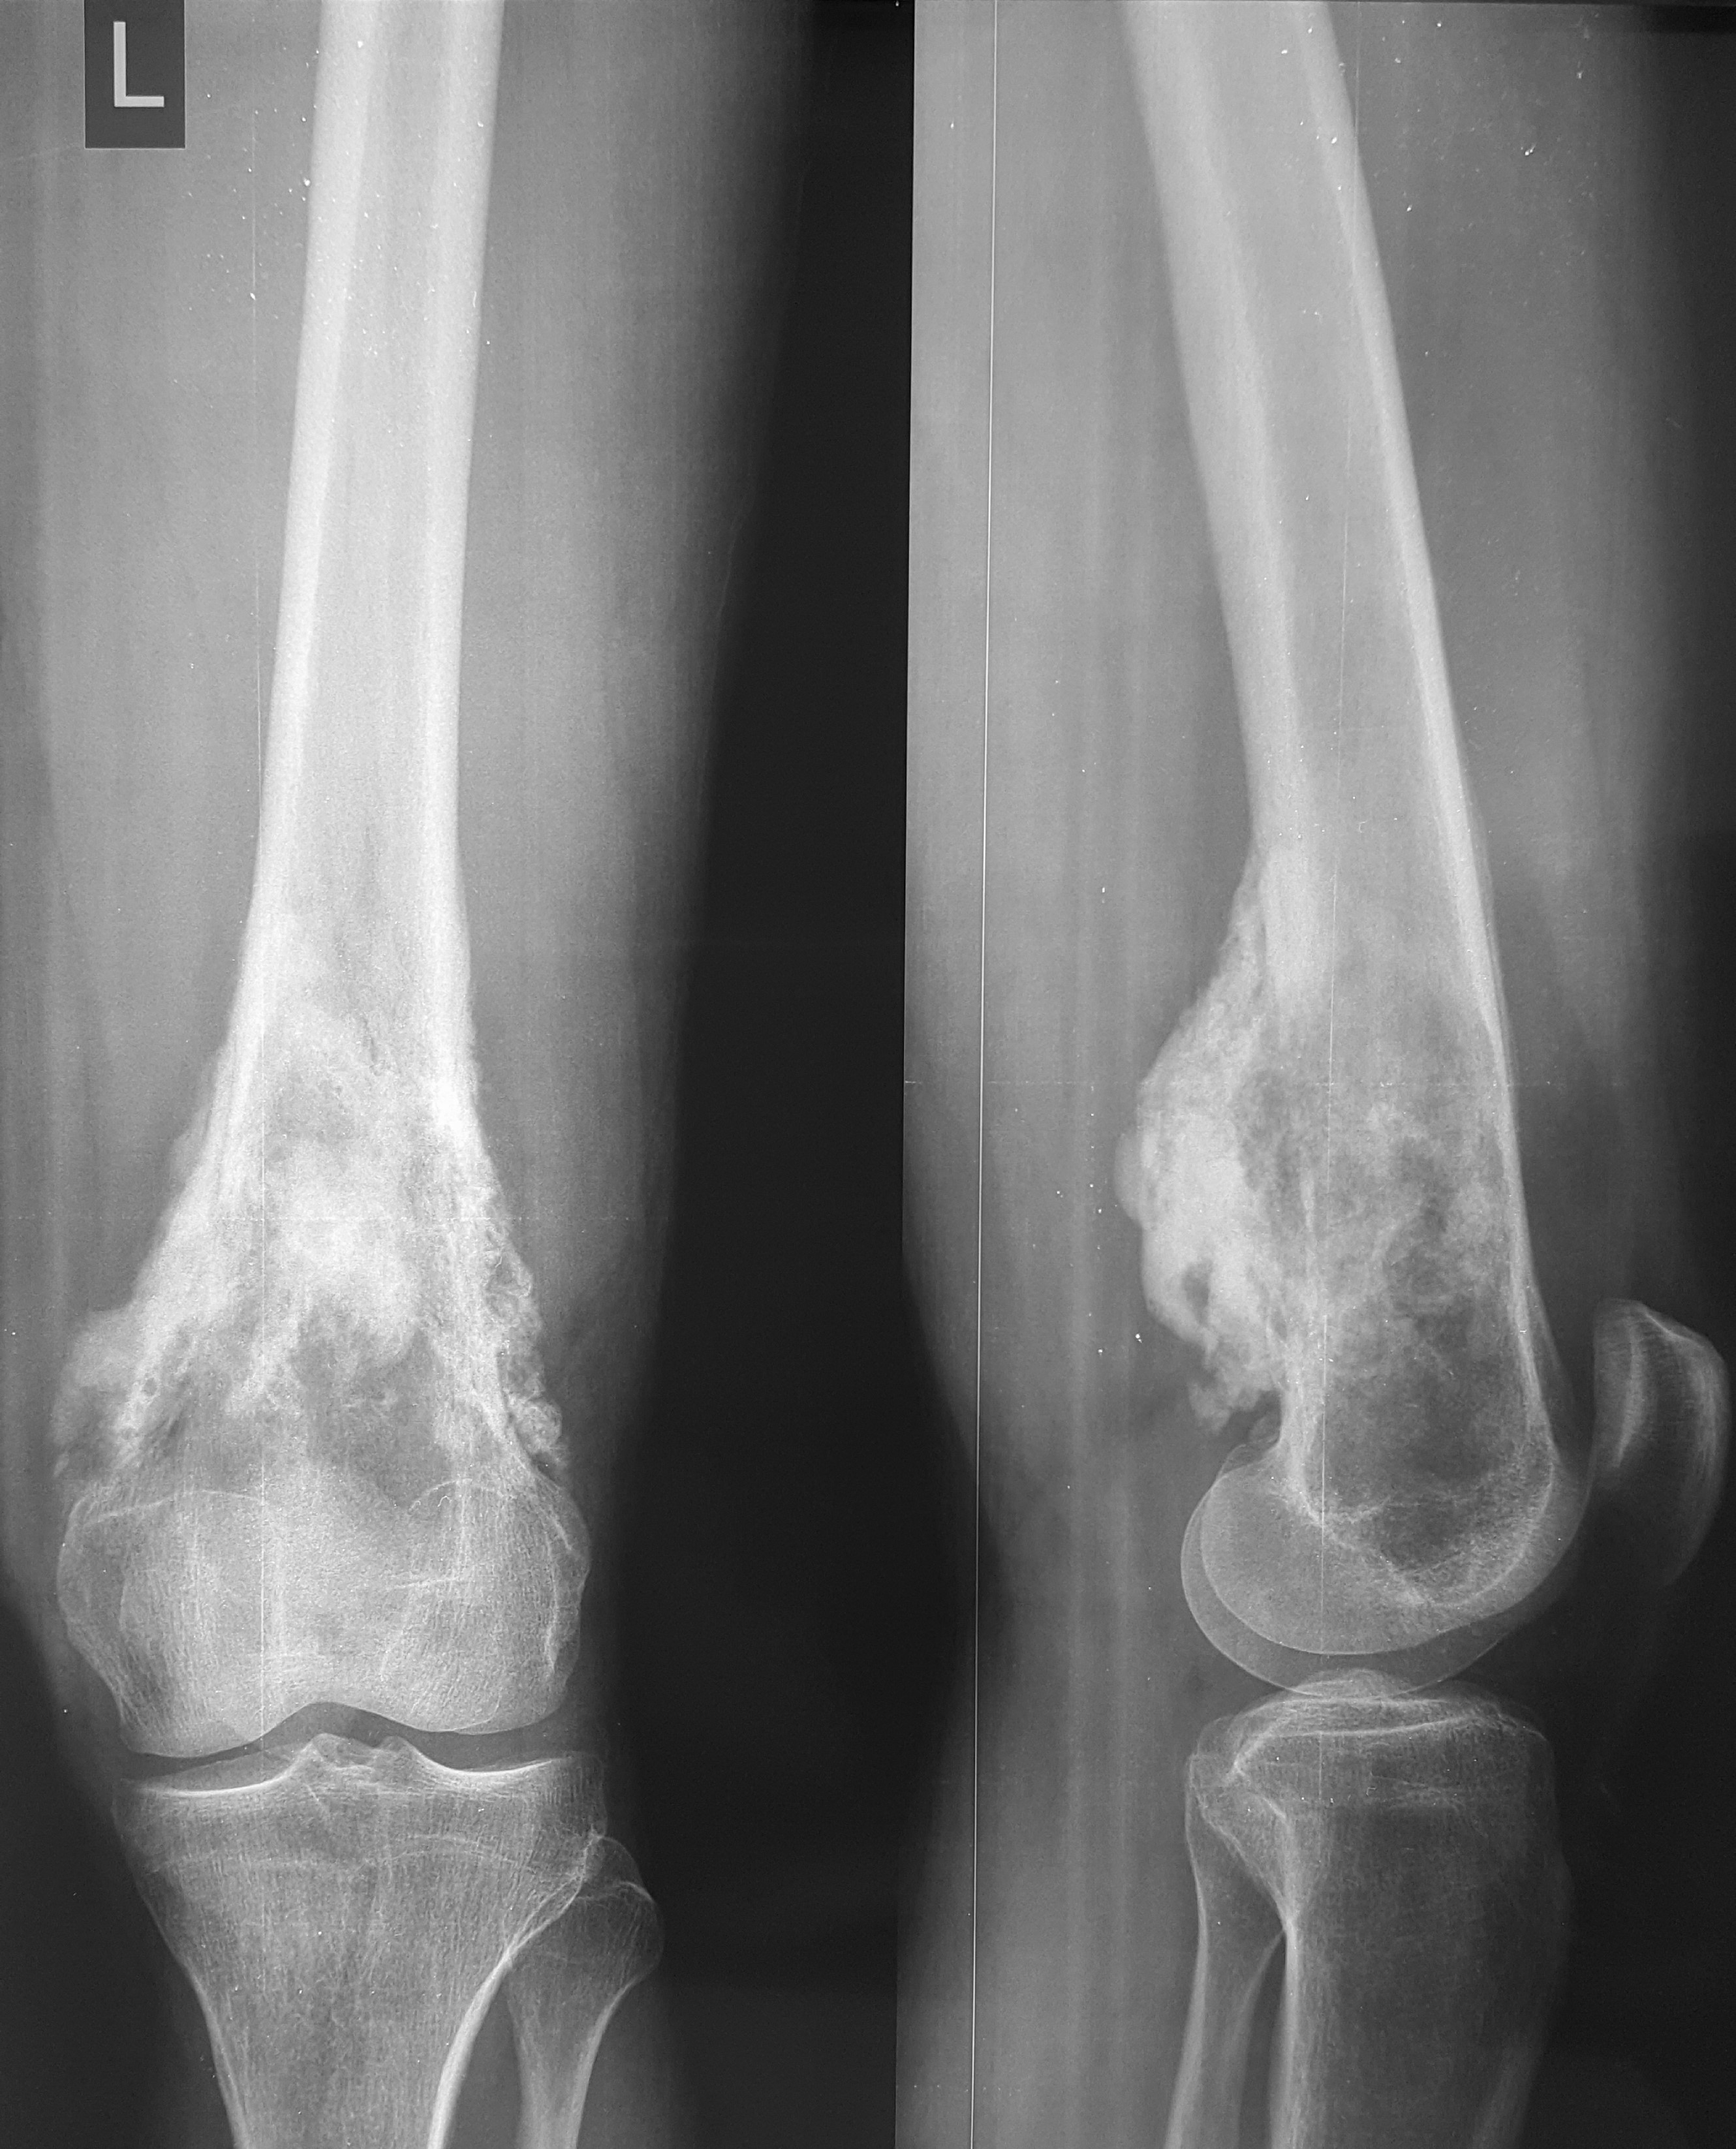

2. Բժշկական տարբեր կենտրոններում հետազոտվելուց հետո՝ 17-ամյա պատանին դիմել է «Նաիրի» ԲԿ։ Համապատասխան հետազոտություններ անցնելուց հետո՝ բուժառուի մոտ հայտնաբերվել է ոլոքի օստեոսարկոմա (ոսկրային քաղցկեղ): Նախավիրահատական բուժում ՝ քիմիոթերապիա, ստանալուց հետո՝ «Նաիրի» ԲԿ ում կատարվել է օրգանապահպան վիրահատություն : Հեռացվել են ծնկահոդն ու ոլոքի վերին երորդականը: Առաջացած դեֆորմացիան շտկել է Եվրոպայից պատվիրված էդոպրոթեզով, որը հնարավորություն է տվել պահպանել վերջույթի գործառույթը՝ քայլել, վազել և այլն։ Հետվիրահատական շրջանում բուժառուն ստացել է քիմիոթերապիա։ Այժմ գտնվում է բժիշկների հսկողության ներքո։

Վիրահատությունից առաջ